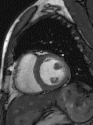

心脏成像 --- 压缩感知电影

自由呼吸,无需屏气

捕获全心动周期数据

临床价值

成像速度和图像质量同时提升

定量数据更精准

心脏MR适用人群更广

实例展示

压缩感知

传统实时

传统分段

心脏电影---房颤病人图像质量对比